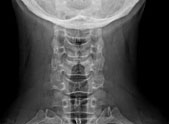

Konventionelles Röntgen des Nervensystems (Neuroradiologie)

• Wirbelsäule

Röntgennativuntersuchungen (Radiographie, Durchleuchtung) haben mit Einführung moderner Schnittbildverfahren (CT, MRT) an Bedeutung verloren und werden bei uns nur noch zur Beurteilung primärer Knochenprozesse, knöcherner Fehlbildungen, degenerativer Veränderungen und Traumafolgen von Schädel und Wirbelsäule eingesetzt.

Film: Wirbelsäule